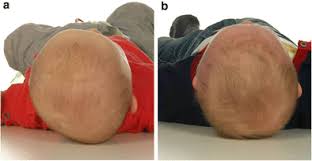

إذا لاحظت تسطحًا واضحًا في مؤخرة الرأس أو جانبه، أو عدم تماثل في شكل الوجه أو موضع الأذنين، فمن الأفضل استشارة مركز متخصص.

عادةً يبدأ علاج الخوذة الطبية بين عمر ثلاثة وستة أشهر، وهي الفترة التي تحقق أعلى نسبة تحسن. التقييم الأولي يشمل الفحص البصري واللمس لتحديد درجة التشوه وأسبابه.

هل الخوذة الطبية ضرورية دائمًا لعلاج تشوهات الرأس؟

الخوذة ليست شرطًا أساسيًا لكل الحالات. في الزيارة الأولى يتم تقييم درجة التشوه. إذا كان بسيطًا، قد يوصي الطبيب بتغيير وضعيات النوم، وزيادة وقت الاستلقاء على البطن تحت الإشراف، وعلاج أي تيبّس في عضلات الرقبة.

في الحالات المتوسطة إلى الشديدة، قد يُقترح استخدام خوذة طبية مخصصة تساعد على توجيه نمو الجمجمة بشكل متوازن. القرار يعتمد على عمر الطفل ودرجة التشوه.